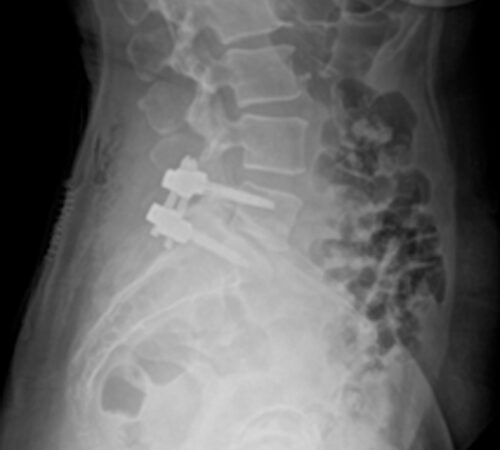

DIAGNOSI:

STENO-INSTABILITA’ LOMBARE MEDIANA

Risonanza magnetica lombare pre-operatoria

Intervento chirurgico eseguito:

PROCEDURA PLIF: POSTERIOR LUMBAR INTERBODY FUSION

Stabilizzazione vertebrale percutanea L4-L5 + introduzione di cage intersomatica PLIF Radiografia lombare post-operatoria